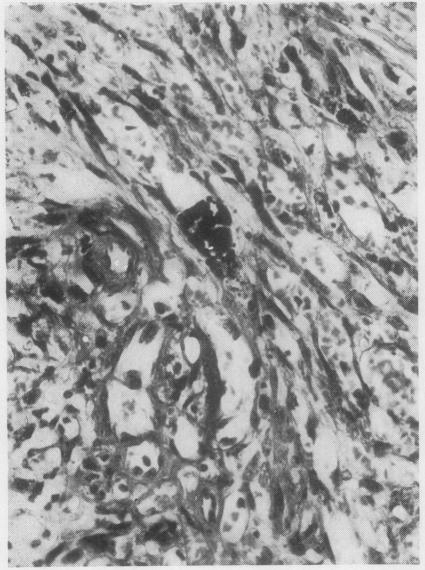

A comparison has been made between two vasoformative lesions, Kaposi's sarcoma and granuloma pyogenicum, as they are encountered in Uganda. Both are predominantly skin lesions arising in the distal extremities, may resemble each other clinically, and are widespread in their distribution in Ugandan communities. They bear a reciprocal relationship to each other as regards age and sex incidence, Kaposi's sarcoma being mainly a disease of adult males and granuloma pyogenicum a disease of immature males and females. Histologically there are many similarities between them, the essential difference being the presence of a spindle-cell sarcomatous element in Kaposi's sarcoma. The clinical behaviour reflects this difference in that granuloma pyogenicum develops quickly and appears to be self-limiting, while Kaposi's sarcoma is slowly progressive and shows much less tendency to regress. On the basis of these findings it is concluded that, although these two lesions may be completely unrelated, it is possible that both represent a response of the vasoformative elements in the skin to a similar form of initiating stimulus and that hormonal or sex-linked genetic factors determine which lesion will develop in response to this stimulus. The presence of intracytoplasmic inclusion in the tumour cells of Kaposi's sarcoma might be of significance in the histogenesis of this tumour, and of value in its histological differentiation from granuloma pyogenicum.

对乌干达出现的两种血管形成性病变——卡波西肉瘤和脓性肉芽肿进行了比较。两者主要都是发生在四肢远端的皮肤病变,在临床上可能彼此相似,并且在乌干达社区中分布广泛。它们在年龄和性别发病率方面呈反比关系,卡波西肉瘤主要是成年男性的疾病,而脓性肉芽肿是未成年男性和女性的疾病。组织学上它们有许多相似之处,本质区别在于卡波西肉瘤中存在梭形细胞肉瘤成分。临床行为反映了这种差异,脓性肉芽肿发展迅速且似乎有自限性,而卡波西肉瘤进展缓慢且消退倾向小得多。基于这些发现得出结论,尽管这两种病变可能完全无关,但两者都有可能代表皮肤血管形成成分对类似形式的起始刺激的反应,并且激素或性连锁遗传因素决定了对这种刺激会产生哪种病变。卡波西肉瘤肿瘤细胞中胞质内包涵体的存在可能对该肿瘤的组织发生具有重要意义,并且在其与脓性肉芽肿的组织学鉴别中具有价值。